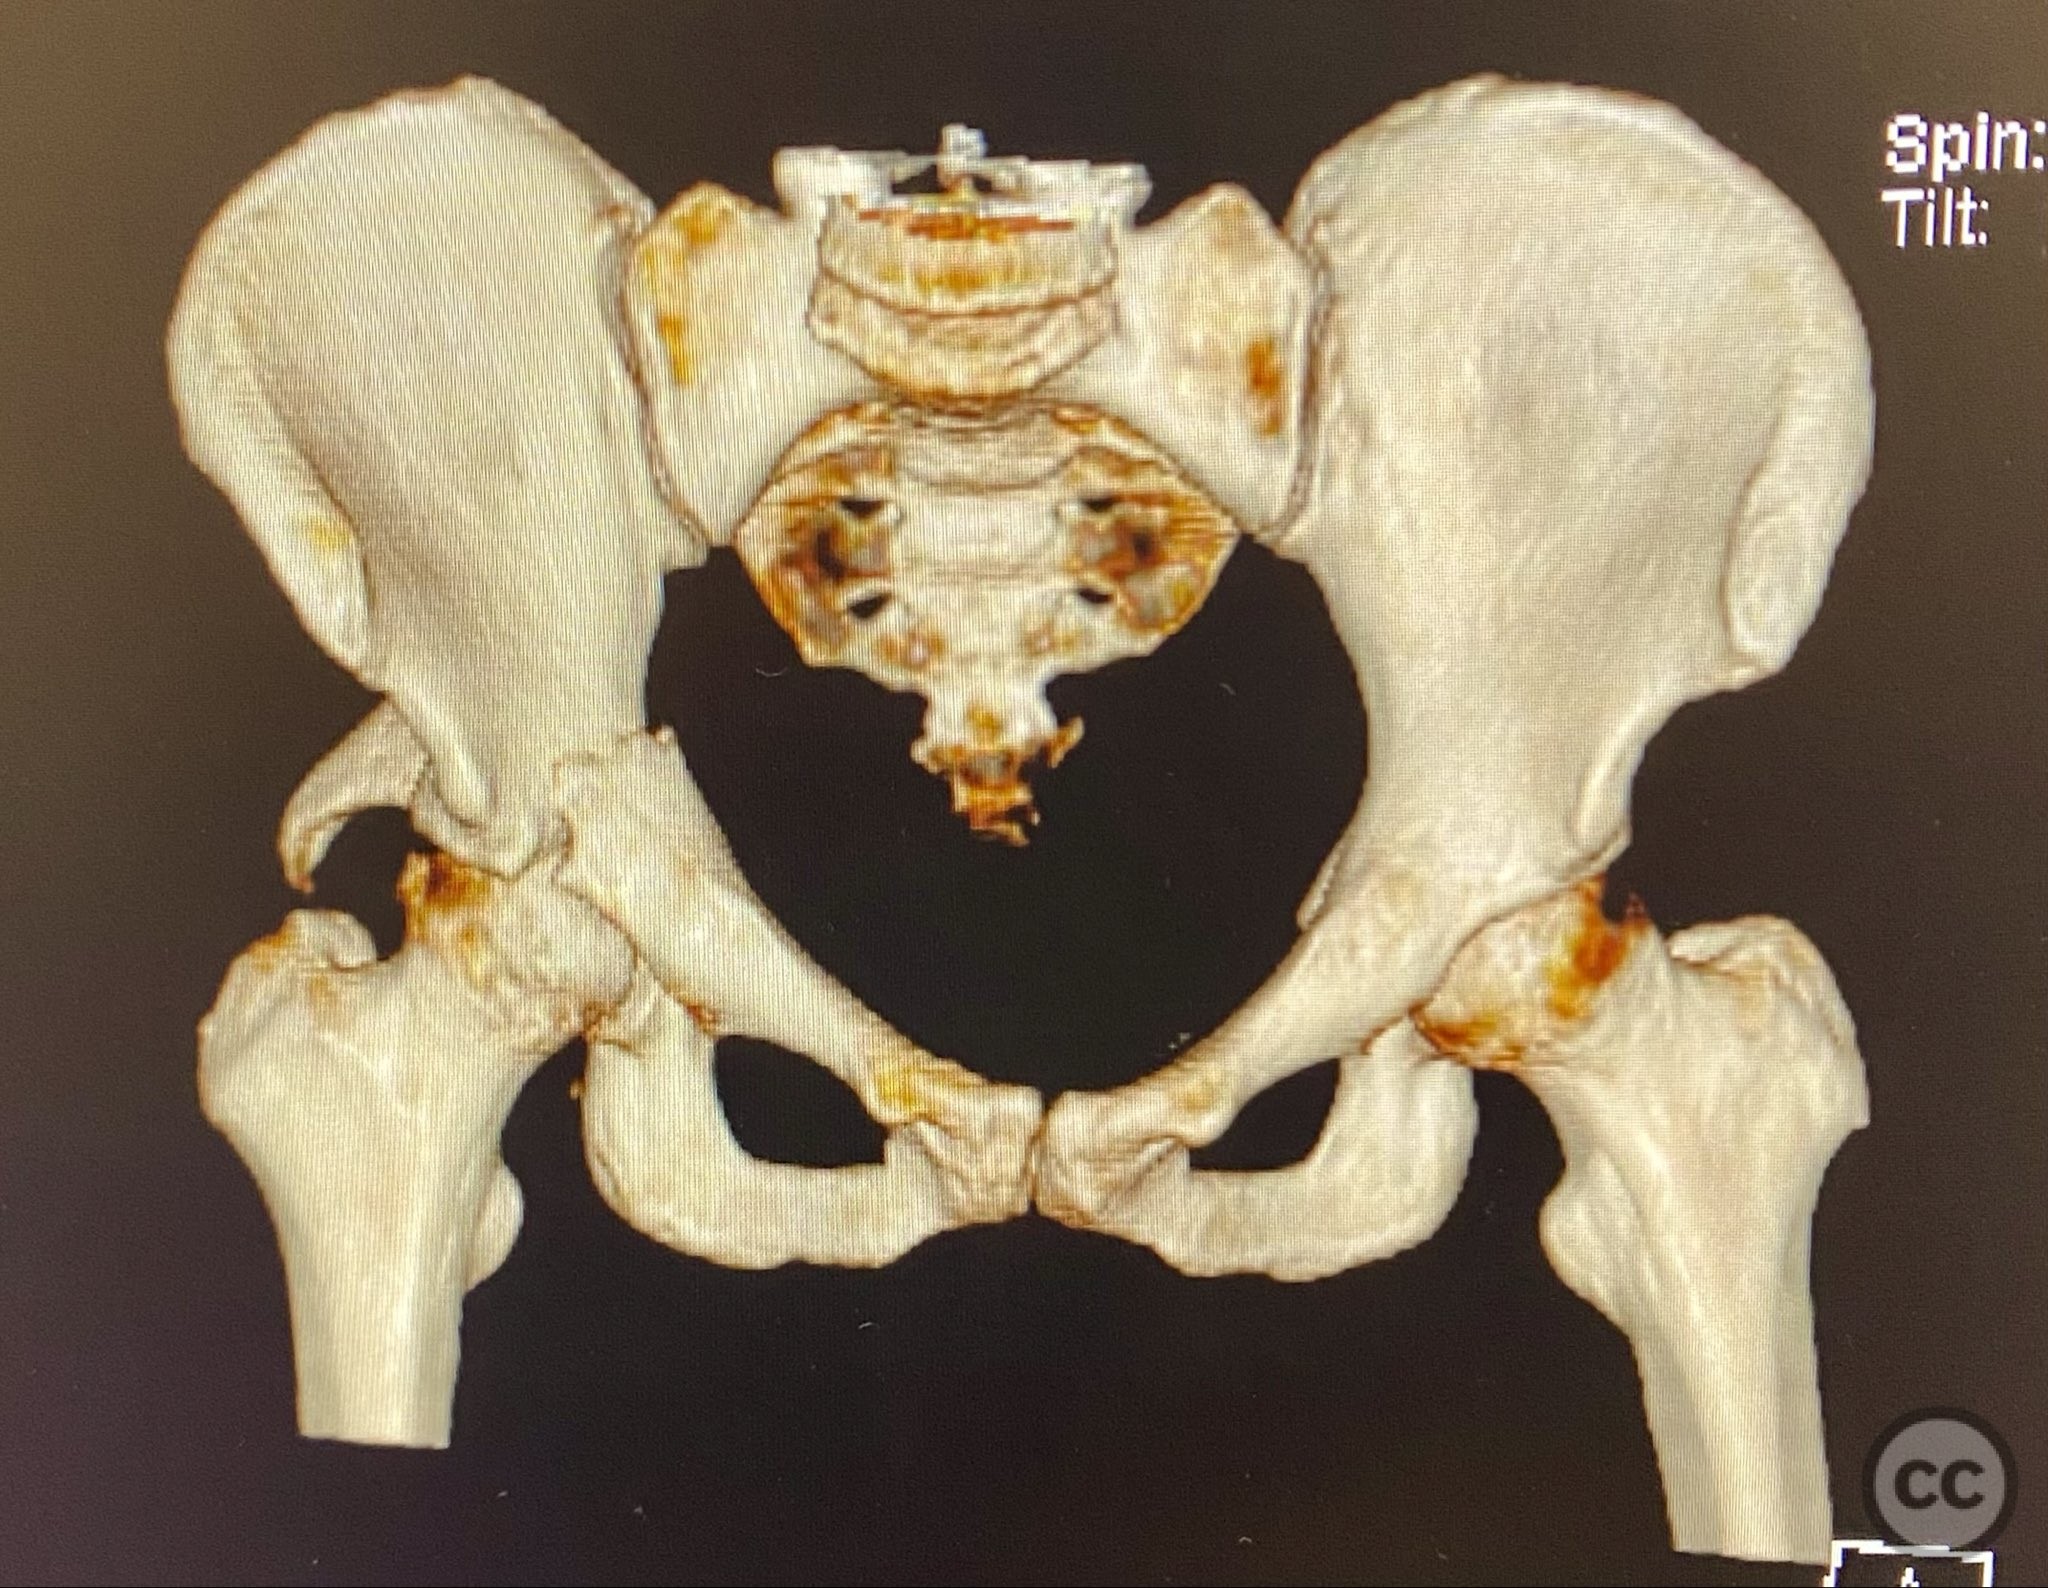

acetabulum fracture

türkiye, Turkey

Pelvis - AO/OTA 6x